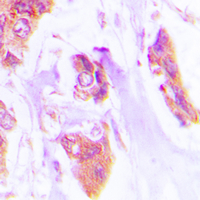

Immunohistochemical analysis of Cardiotrophin-1 staining in human lung cancer formalin fixed paraffin embedded tissue section. The section was pre-treated using heat mediated antigen retrieval with sodium citrate buffer (pH 6.0). The section was then incubated with the antibody at room temperature and detected using an HRP conjugated compact polymer system. DAB was used as the chromogen. The section was then counterstained with haematoxylin and mounted with DPX.